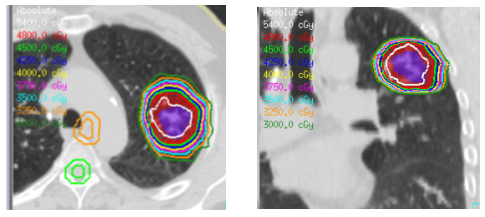

Figure C: 7 month post-SBRT CT scan.

One month post SBRT the patient had no clinical or radiographic signs of radiation pneumonitis. A chest CT at 3months revealed no evidence of recurrent or progressive disease and his concurrent visit was unremarkable. His 7months post-treatment CT revealed a slight decrease in lesion size with spiculation and dendritic extensions into the adjacent lung, extending to the pleura, with new soft tissue architectural distortions, most consistent with radiation changes.